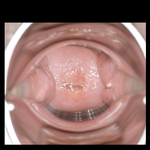

そして立ちポーズでバイブがズブリ。自分から腰をグラインド。バイブを膣奥まで咥え込んで善がり狂う。続いてクスコがズブリ。肉厚でプックリとした子宮口。AV向きの子宮だ。